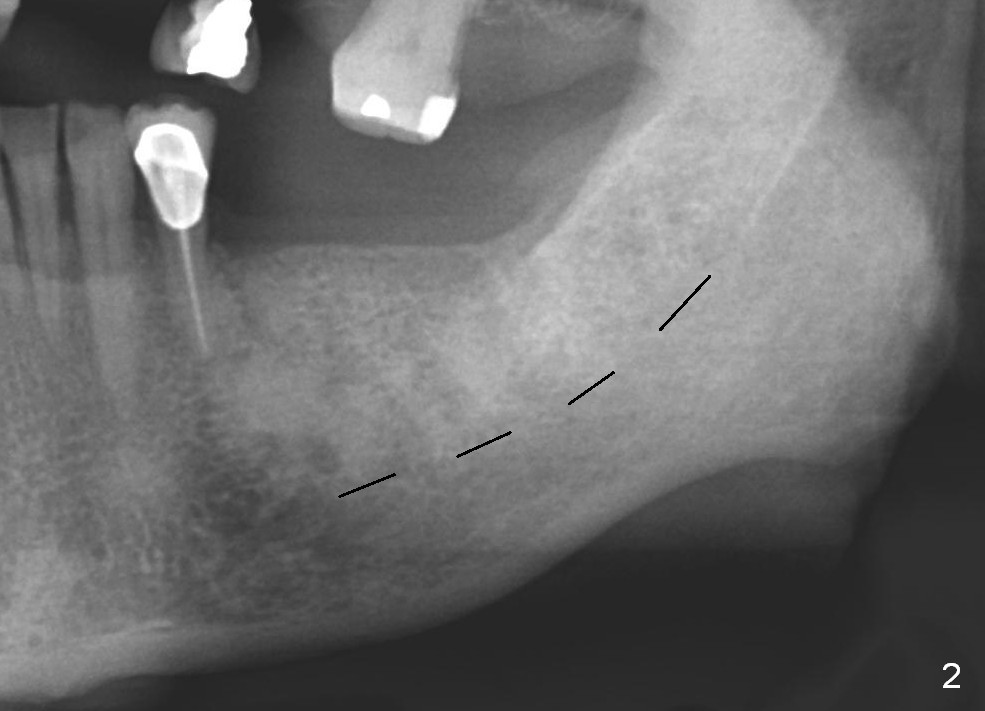

After cementation of crown at #3 and implant placement at #6, the 70-year-old lady will return for #18 and 20 implant placement and possible an immediate provisional (fixed partial denture) FPD (Fig.1,2). Before incision, start osteotomy 5 mm distal to a surgical stent (with #19 as the most distal tooth) and at #18. After incision, the initial bone depth is 11 mm (Fig.3) and insert parallel pins with depth marks for PA. If there is enough bone and bone density is low, extend the depth to 14 mm. Tatum tapered implants are going to be used. Which set of drills should be opened? Set speed at 50 RPM. Fig.3 is long horizontally. It should have been taken with #1 sensor. Beside, she is skinny. The dental arches are narrow.